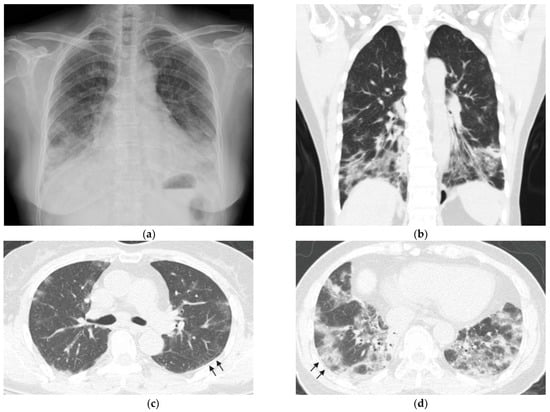

A 67-year-old non-smoking woman was admitted to our hospital for progressive dyspnea that lasted for 1 week. She had a history of chronic hepatitis C, diabetes mellitus, and endometrial cancer after hysterectomy without recurrence in 2 years. She was well until 2 months before admission, when she experienced fever, dyspnea, and productive cough. She was admitted to another hospital, where she underwent a chest radiograph that revealed reticular opacities and consolidations in the bilateral lower lungs (Figure 1a). Chest computed tomography (CT) revealed a predominance of multifocal ground-glass opacities in bilateral basal lungs with subpleural sparing patterns, suggesting nonspecific interstitial pneumonia (NSIP; Figure 1b–d). Blood testing was positive for anti-CTD antibodies, and detailed serologic testing was not conducted. Her condition improved substantially after treatment with antibiotics and methylprednisolone for possible pneumonia and ILD. After the patient was discharged from hospital, she received prednisolone (10 mg/day) and azathioprine (50 mg/day) at a rheumatology outpatient clinic. No specific diagnosis of CTD was made.

Figure 1. Chest imaging at initial presentation (a) Chest radiograph revealed reticular opacities and consolidations in bilateral lower lungs. (bd) Computed tomography scans revealed subpleural sparing patterns (arrows) and multifocal ground-glass opacities in bilateral basal distribution, indicating nonspecific interstitial pneumonia.